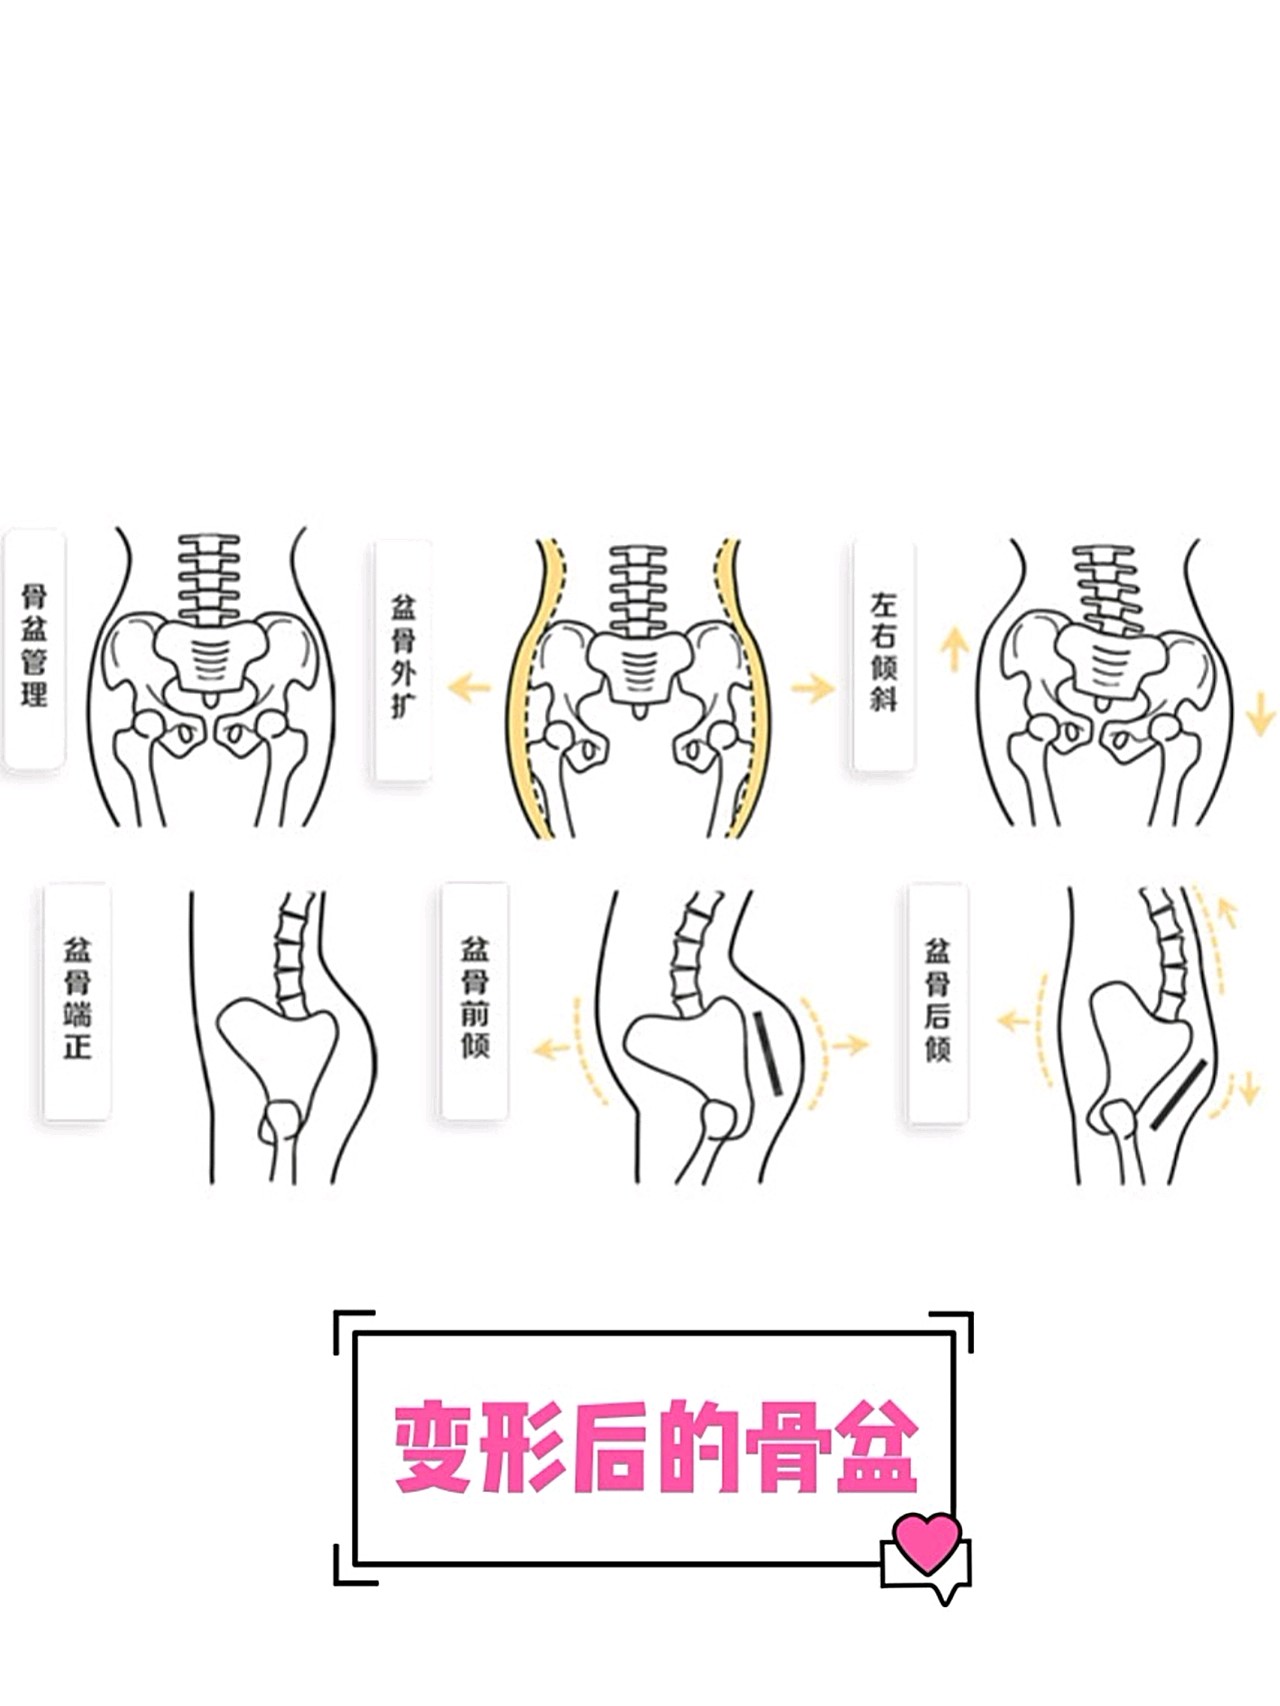

骨盆倾斜怎么判断哪些人容易骨盆倾斜附2招自我矫正法

健康坏习惯让骨盆经历了啥

眼皮一单一双眼睛不等大是您的骨盆移位造成

骨盆倾斜原因分析,你正在用哪个方式伤害自己的骨盆?——徐州脊柱侧弯

其它 盆骨变形的危害 写美篇一,骨盆变形容易导致脊椎弯曲,压迫神经

每天沉迷翘二郎腿,你的骨盆还好吗?